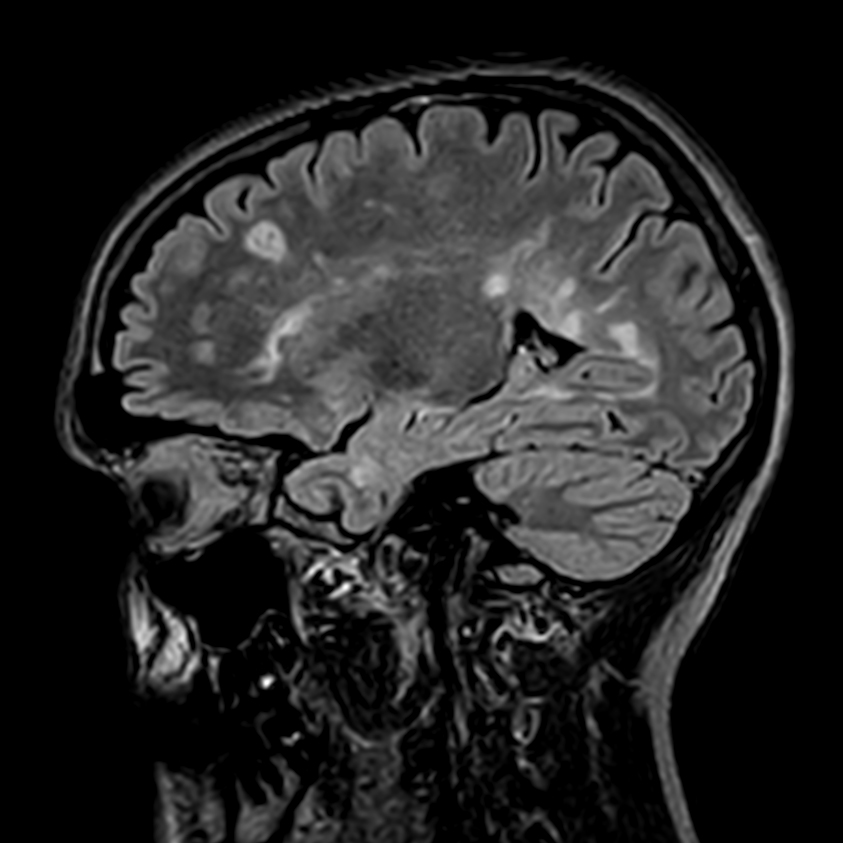

Patient with multiple brain lesions. ExamCard includes Compressed SENSE to shorten the exam time, 3D scans to acquire high resolution data in multiple directions in only one single scan and 4D-TRAK for dynamic contrast-enhanced MR Angiography enabling high spatial and temporal resolution simultaneously.

3D T2w FLAIR Compressed SENSE